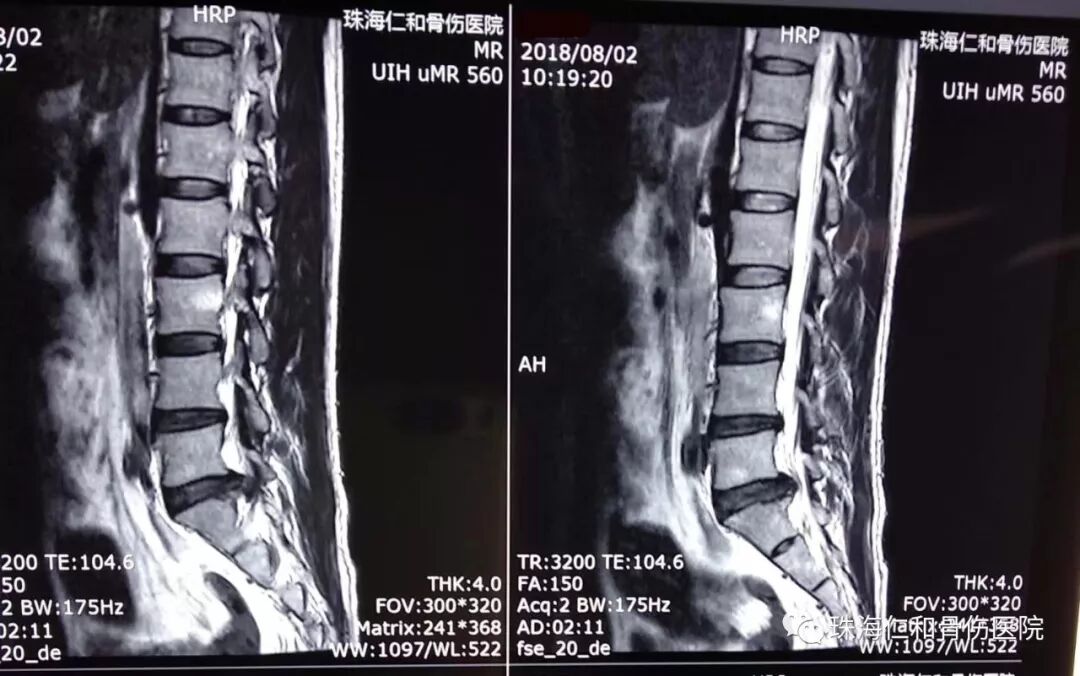

腰腿痛,工作和生活常见多发病。仁和骨伤医院脊柱专科开展特色手法、针灸,中药烫包和中药泥灸等中西医结合系列保守治疗。使得众多腰腿痛(腰椎间盘突出症)病患者好转满意而归。然而总有一些顽固腰腿痛,需要通过特殊治疗手段解决。就像我们这位阮老师,出现腰痛和右下肢麻痛反反复复已经十多年,诊断是腰椎盘突出症,也曾到省内和市内各大医院求医问诊过,但都无法使得腰腿痛得以解除,教书育人工作、日常生活都受到影响。来到仁和骨伤医院,住院伊始就抗拒手术治疗,于是仁和的脊柱专家倾情为他多措并举的保守施治,可是因为椎间盘突出严重,效果欠佳,阮老师经过对微创手术充分了解,同意仁和医院为他设计的微创手术治疗方案,脊柱孔镜椎板间入路髓核摘除、神经根管扩大、纤维环成型术。手术相当顺利,术后阮老师就觉得腰痛和腿痛症状消失了,术后第二天就可以带腰围保护下床开始活动,阮老师往日久违的笑容又回来了。相信不久的日子,在仁和专业的康复指导下,阮老师很快会回到工作岗位、开始崭新的生活。